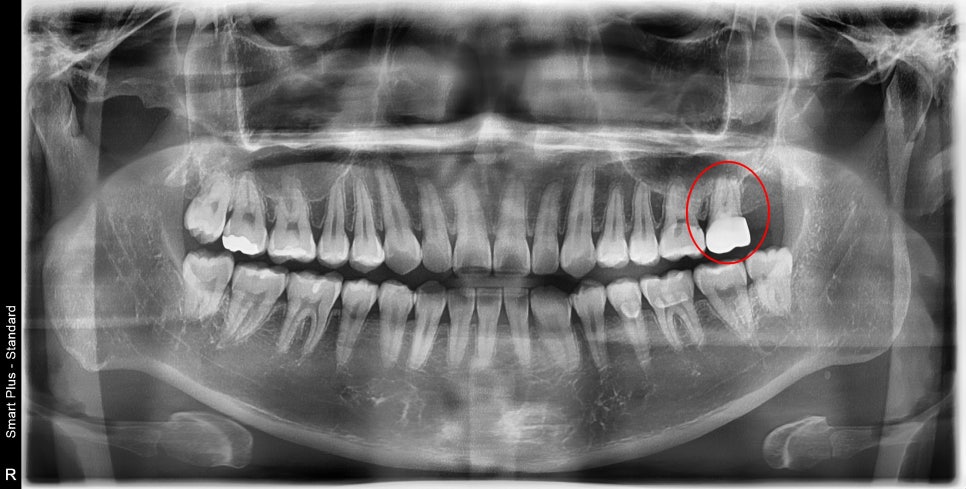

사진에 표시된 화살표처럼

치아를 가로지르는 선명한 크랙 즉, 금 간 것이 보이실 겁니다.

이상하게도 그때도 증상이 거의 없으셨고,

환자분께서 발치는 거부감이 있으셔서

마지막 시도로 MTA를 사용한 케이스였는데

얼마 전에 치료 후 1년 되는 시기에 내원을 해주셨습니다.

특별하게 엑스레이, 육안상, 검사상에서도

특별한 문제는 발견되지 않았습니다.

예후가 많이 좋지 않았지만 1년째까지 너무 다행이지만

한편으로는 자주 내원하게 해드려서

교합이나 증상 체크를 잘해드려야겠다는 생각도 들었습니다.

지금도 이 정도로 금이 가서 오신 환자분이 계시다면

저는 발치를 권해드릴 것 같습니다.

MTA가 만능이 아니라 여러 상황이 재료의 장점을 극대화해줬던 것 같습니다.